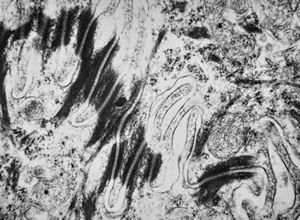

F,41y. | synovial metaplasia - capsule of implantate

F,41y. | synovial metaplasia - capsule of implantate

F,41y. | synovial metaplasia - capsule of implantate

F,41y. | synovial metaplasia - capsule of implantate

F,41y. | synovial metaplasia - capsule of implantate

F,41y. | synovial metaplasia - capsule of implantate

F,41y. | synovial metaplasia - capsule of implantate

F,41y. | synovial metaplasia - capsule of implantate

F,41y. | synovial metaplasia - capsule of implantate